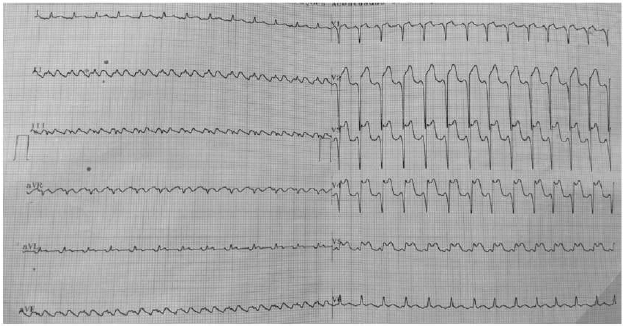

Paciente de 58 anos compareceu a um hospital regional do interior do Rio Grande do Norte. Durante o atendimento, relatou ter sentido dor precordial em aperto, associada à sudorese e mal-estar, com início há 5 horas, mas com piora há 20 minutos, após quadro de taquicardia. Foi medicado com AAS 300 mg e clopidogrel 300 mg, 5 mg de dinitrato de isossorbida sublingual, sem melhora da dor. Ao exame físico, apresentou: PA 110x60 mmHg, FC 156 bpm, auscultas cardíaca e pulmonar normais, boa perfusão periférica.

Realizou o eletrocardiograma reproduzido abaixo.

Nesse momento, o tratamento é